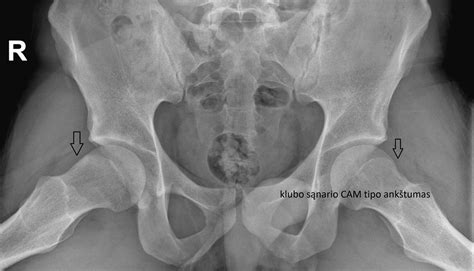

Klubo sąnario artrozė III stadija ir invalidumas

Klubo sąnario artrozė